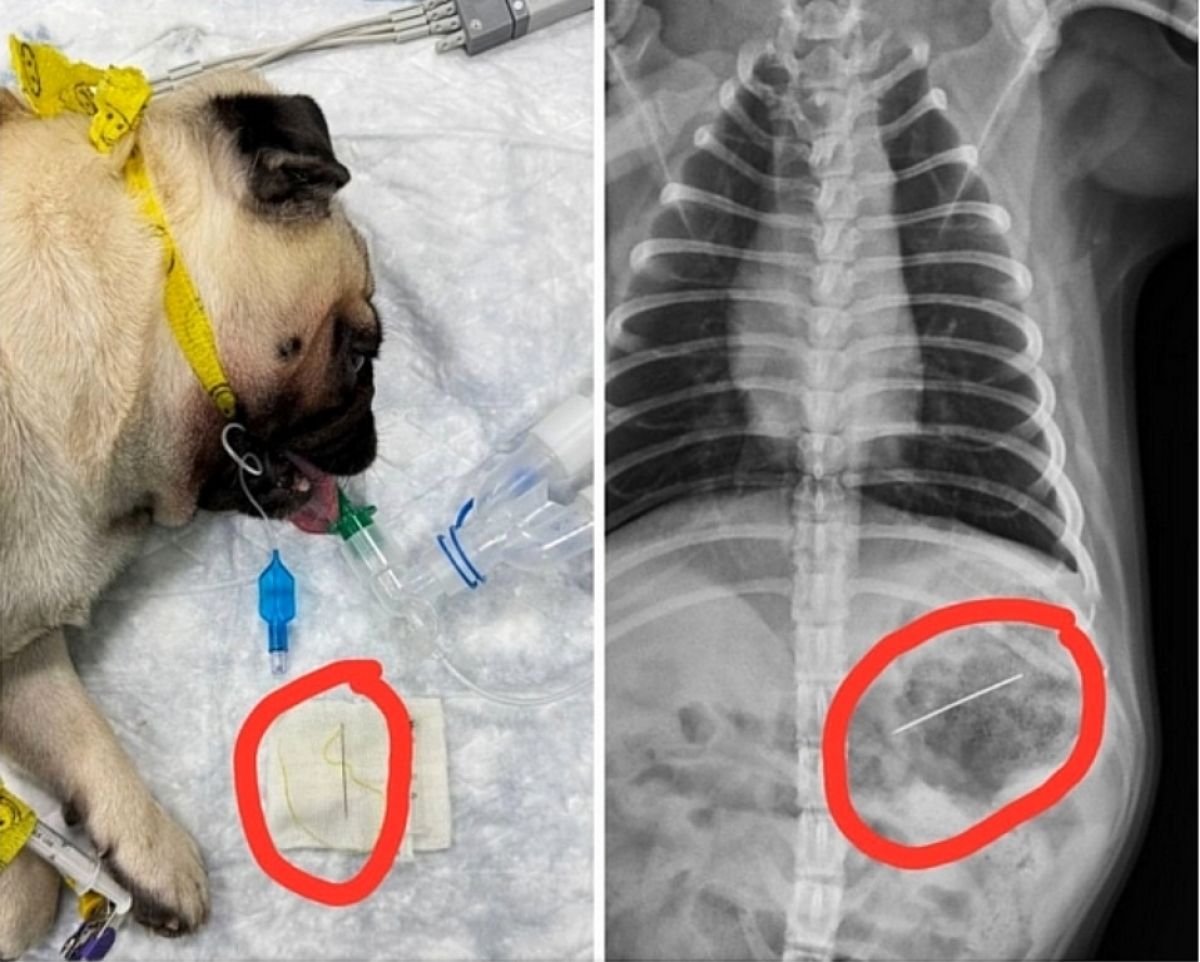

Липецкие ветеринары смогли спасти любознательного мопса по кличке Джамбо, когда тот проглотил иголку с ниткой.

«Состояние питомца на первый взгляд было удовлетворительным, но мы понимали, что счет может идти на часы, – поделились впечатлениями в клинике. – Рентген подтвердил наши худшие опасения: в полости желудка отчетливо виднелся металлический объект».

Хирург Сергей Бачурин решил, что нужно попытаться извлечь опасный предмет, избежав травмирующей полостной операции. Хотя острый конец иглы мог легко проколоть стенки желудка или кишечника. С помощью эндоскопа – гибкой трубки с камерой и манипуляторами – доктор Бачурин провел операцию прямо через пасть пациента. Под контролем анестезиолога Ольги Кондратовой он смог «поймать» иголку и аккуратно извлечь ее наружу, не оставив на теле Джамбо ни единого разреза.